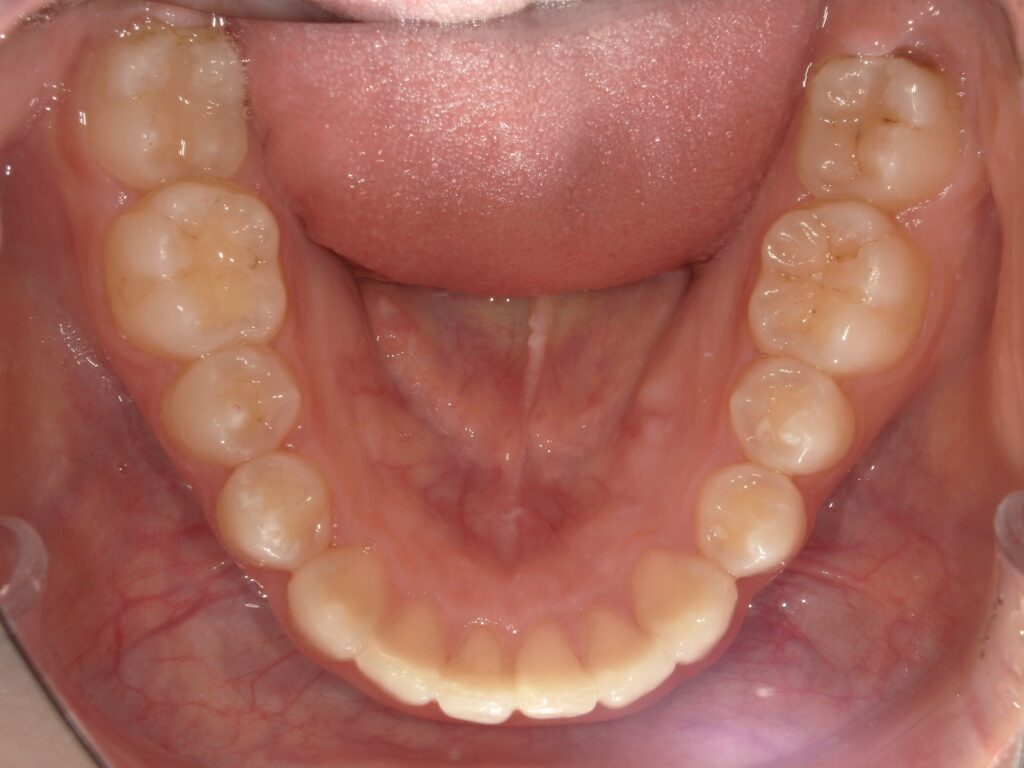

Before

After

ガタつき / かみ合わせ

- 30代男性

- 主訴:前歯のガタつきと噛み合わせを良くしたい

- 矯正方法:インビザラインの非抜歯矯正

- 治療期間:9ヶ月

- 治療費:710,000円

- その他ご要望:治療期間を早くしたい、マウスピースを早く受け取りたい。

- 詳しくはこちら

Before

After

ご相談内容 前歯のガタつきと噛み合わせが気になると30代男性からのご相談 現状と治療方針 前歯のガタつきが見られます。また、下の前歯を上の前歯が大きく被さっているため、下の前歯が見えない過蓋咬合(ディープバイト)が見られます。奥歯をさらに後ろに下げる遠心移動と、歯と歯の間にわずかなスペースを作る方法で矯正を行いました。 治療結果 ガタつきと噛み合わせを9ヶ月で改善できました。 振り返り 今回の患者様は他院で不信感があり、ご紹介という形でセカンドピニオンを受けるために当院にお越しいただきました。お仕事が多忙のため治療期間を早くすることが一番重要なご要望でしたが、全体矯正にも関わらず9ヶ月で矯正を終えることができたことに大変喜んでいただけました。 リスク・副作用 マウスピースの装着時間を守っていただけないと矯正治療に時間がかかり、場合によっては治療がうまく進まない可能性があります。